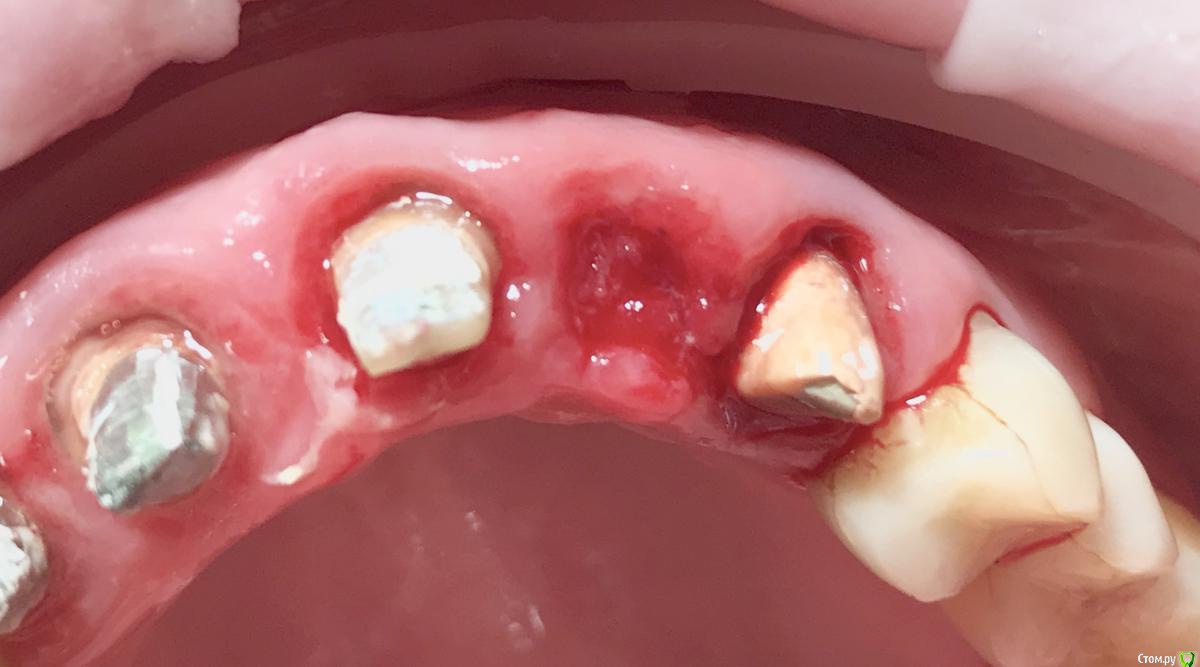

колесников Опубликовано 10 мая, 2019 Поделиться Опубликовано 10 мая, 2019 Удаление с консервацией под мост,закрыто быстрымноймаером. Вид через 3 недели . Удаление повязки,под ней не созревший гранулят,замена на овоид. Следующий визит через месяц,посмотрим будет ли стабилен десневой контур. 3 Ссылка на комментарий